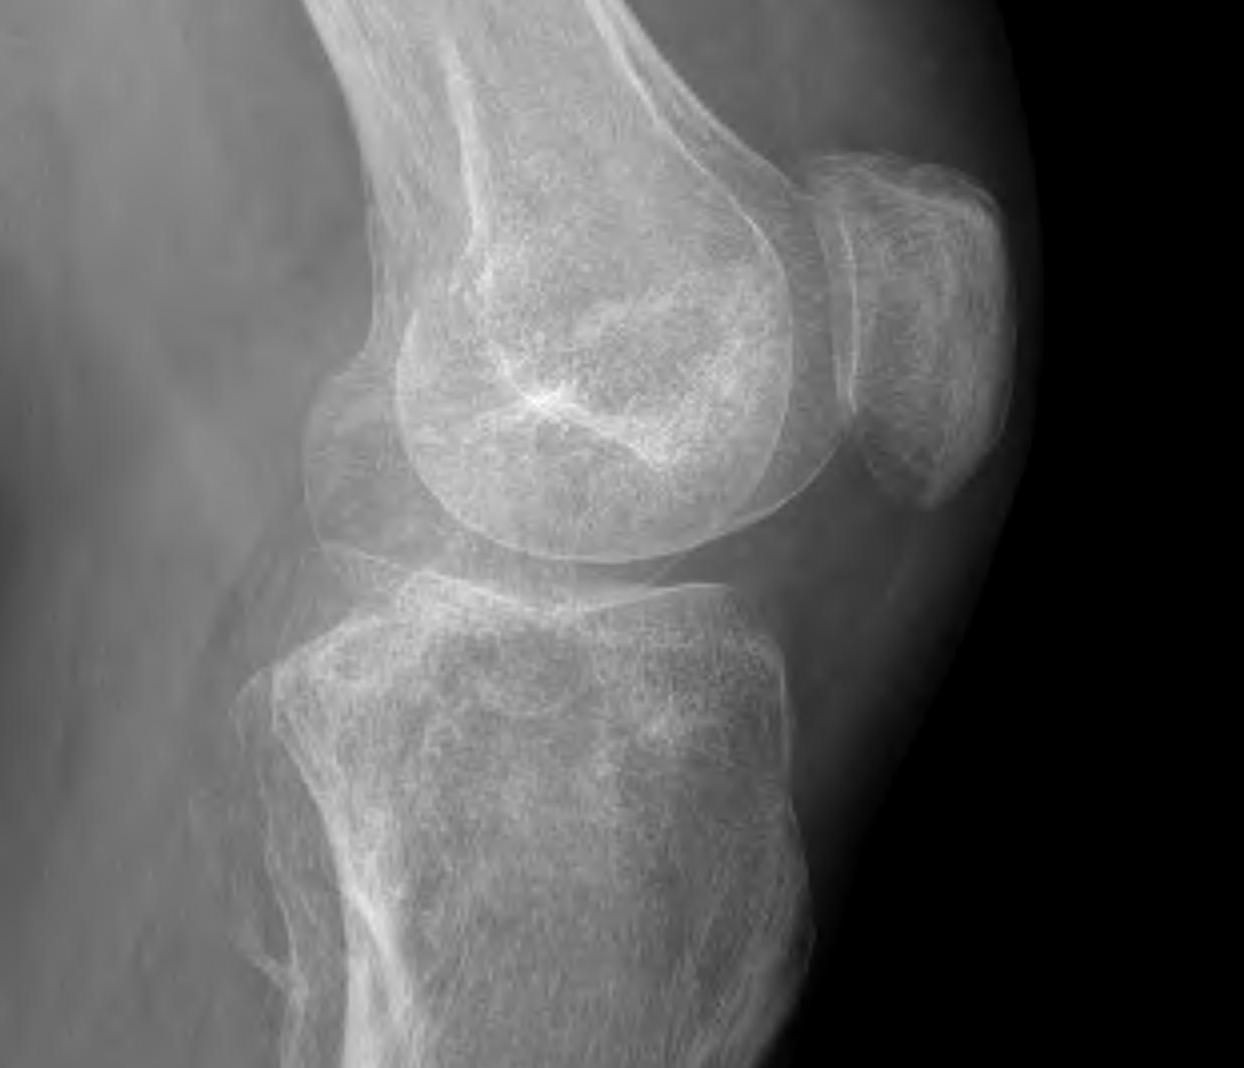

• Cartilage defects

• Background

• Management